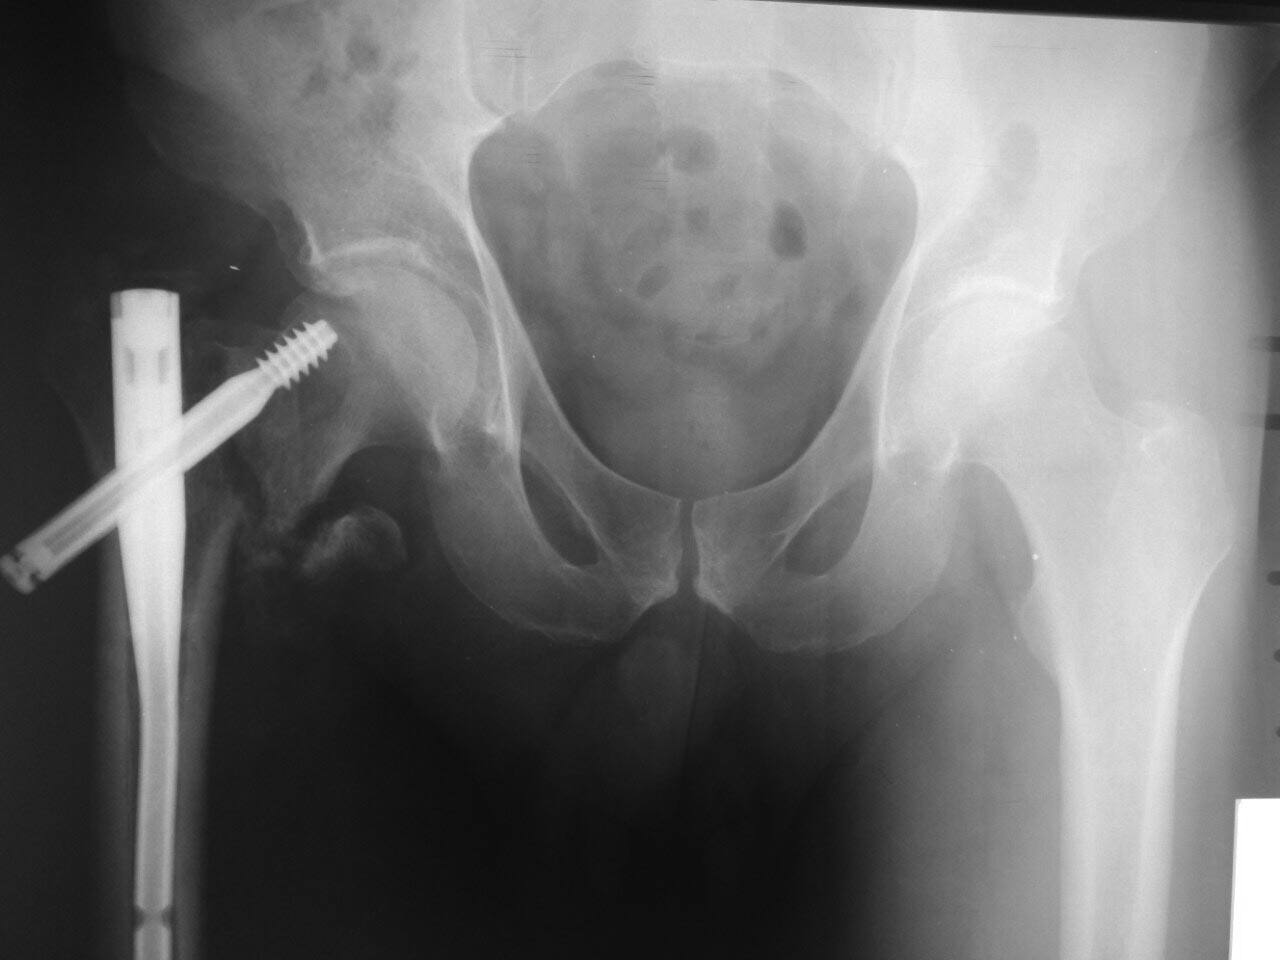

Мужчина 45 лет 1,5 мес

назад прооперирован в одной из клиник в средней полосе. Выполнен

остеосинтез, видимо , Gamma 3. Сказали - ходи. В общем, сейчас ходит на

костылях дозированно нагружая ногу. Вернувшись из отпуска пришёл к нам в

клинику, озадачил коллег)) .

Есть следующие мысли:

1. Удалить гамму, остеосинтез DCS с длинной накладкой и костной

пластикой. 2.Реостеосинтез имеющимся у нас гамма-гвоздём с деротационным

винтом, установив его в правильное положение. Коллеги,

помогите в принятии решения, дополните пробелы в наших изысканиях.